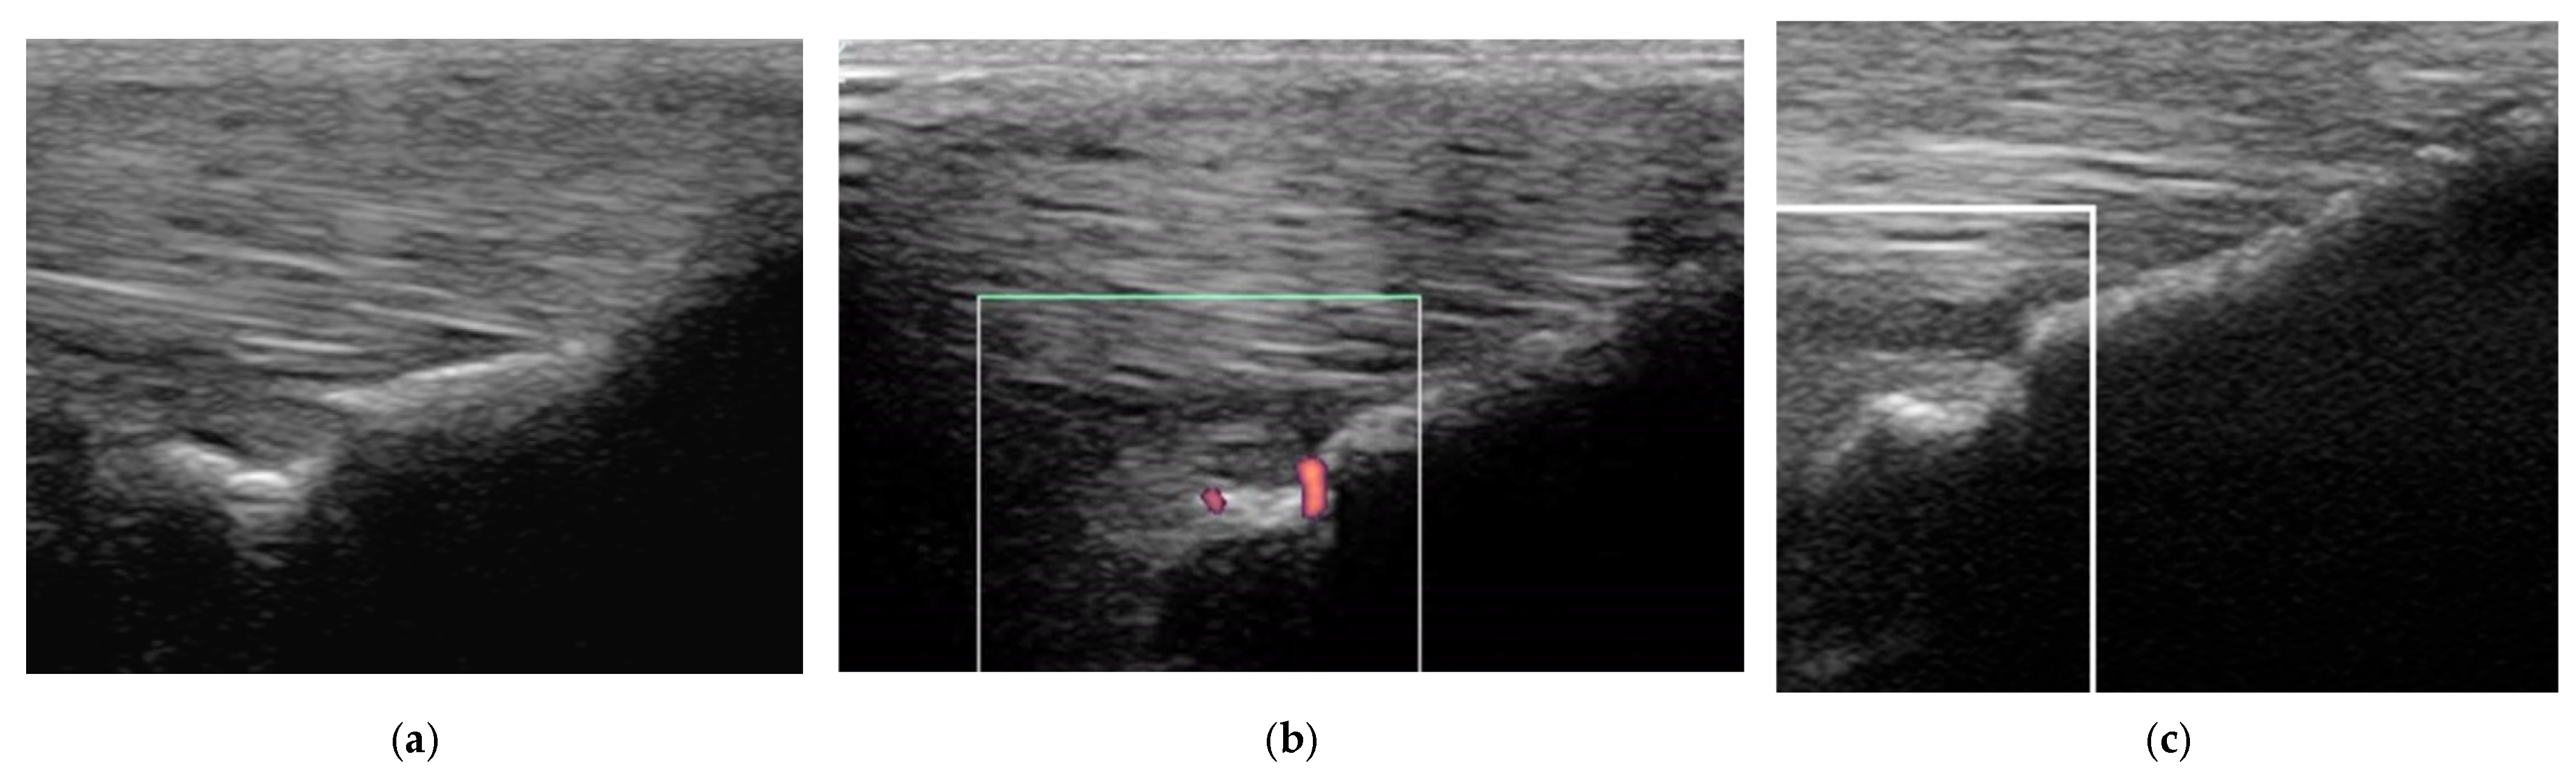

Two horses had recurrent desmitis of the same injured branch as the original injury, having returned to full work, one and four years after the initial injury, respectively (Figure 12). Both horses had a good outcome.

Figure 12. The same suspensory ligament branch as Figure 8, acquired four years after the initial injury. (a) Transverse image at the mid region, (b) transverse power Doppler image at the same level as (a,c) longitudinal power Doppler image of the distal region (proximal is to the left). (a) There is a new injury at a more proximal site (arrow) than the original injury, with mild Doppler activity (b). At the original injury site (c), a hypoechoic lesion is still apparent, but no Doppler signal was detected. There was localised swelling at the injury site, and distension of the metacarpophalangeal joint capsule.